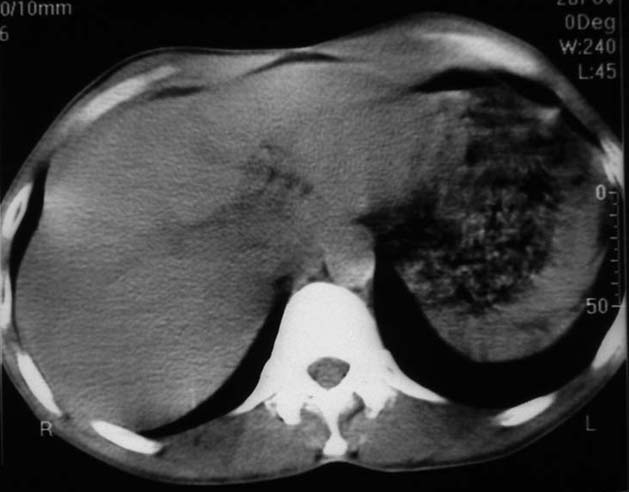

男,50y,右上腹包块痛10天,查:右上腹饱满,右肋下触及6*6cm大小包块,质硬,压痛。患者诉:10天前感冒胸闷,痛,后痛及右上腹部,既往有肝炎病史。

没有增强!只能考虑左叶内侧段巨块型肝癌(外生型)可能性大;胆囊呢?不除外胆囊癌累及肝脏。

我倒是先考虑胆囊癌(肿块型)肝脏受侵可能性大,做个c+

病变位于胆囊窝内,其内密度不均,肝总管及胆总管扩张,胃里面没有清水充盈,不解为什么楼主不做好了准备再做呢,支持:“左叶内侧段巨块型肝癌(外生型)可能性大;不除外胆囊癌累及肝脏”建议增强吧。

考虑:肝左内叶巨块型癌,主动脉旁淋巴结转移.(有一层面似见胆囊受压.)